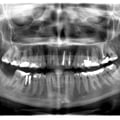

Пацієнт Б (14 років) - множинна ретенція прорізування постійних зубів. Наявність закладки 9-тих зубів